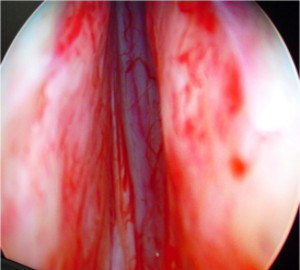

Bladder Tumor